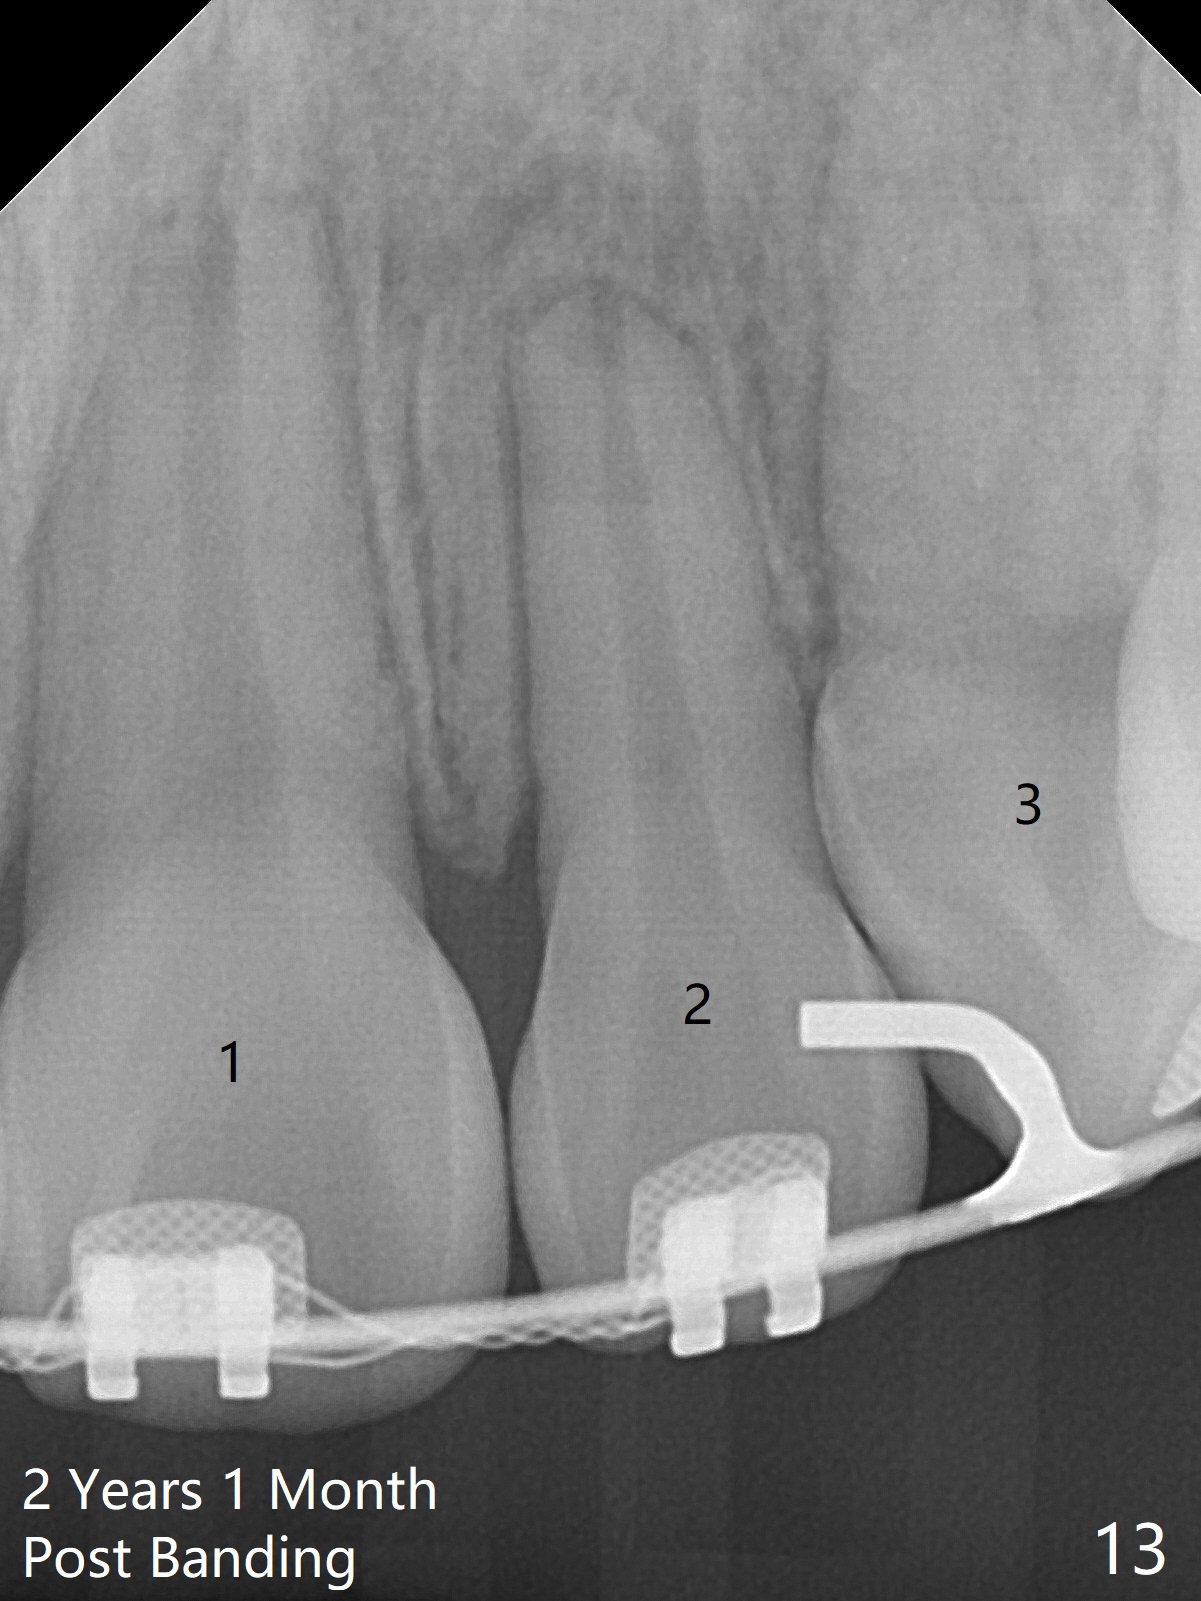

Two weeks post extraction of 4 bicuspids, brackets and bands are placed in 20 teeth (Fig.1-3, 14 niti). No bands are placed at 7s because of short crowns and tight contacts. When 16x16 wires are used, start Class II retraction. The latter is initiated with elastics when 18 ss wires are placed (Fig.4,5). U3s have been distalized with closed springs for 3 months (Fig.6,7). U2s are close to distalization 13 months post banding, 3.5 months post posted wire (Fig,8,9) with overjet (Fig.10). Class II retraction is re-initiated. When the upper incisors are retracted, the anterior overjet remains large. It appears that U6s have been retracted anterior, as indicated by the space between U6/7 (Fig.11), because of no use of U7s as anchors. Brackets are just placed with 18 niti arch wire. They will be retracted distal using the rest of the upper teeth and lower teeth (using Class II retraction) as anchor. There is root resorption of the upper anteriors 2 years 1 month post banding (Fig.12,13).